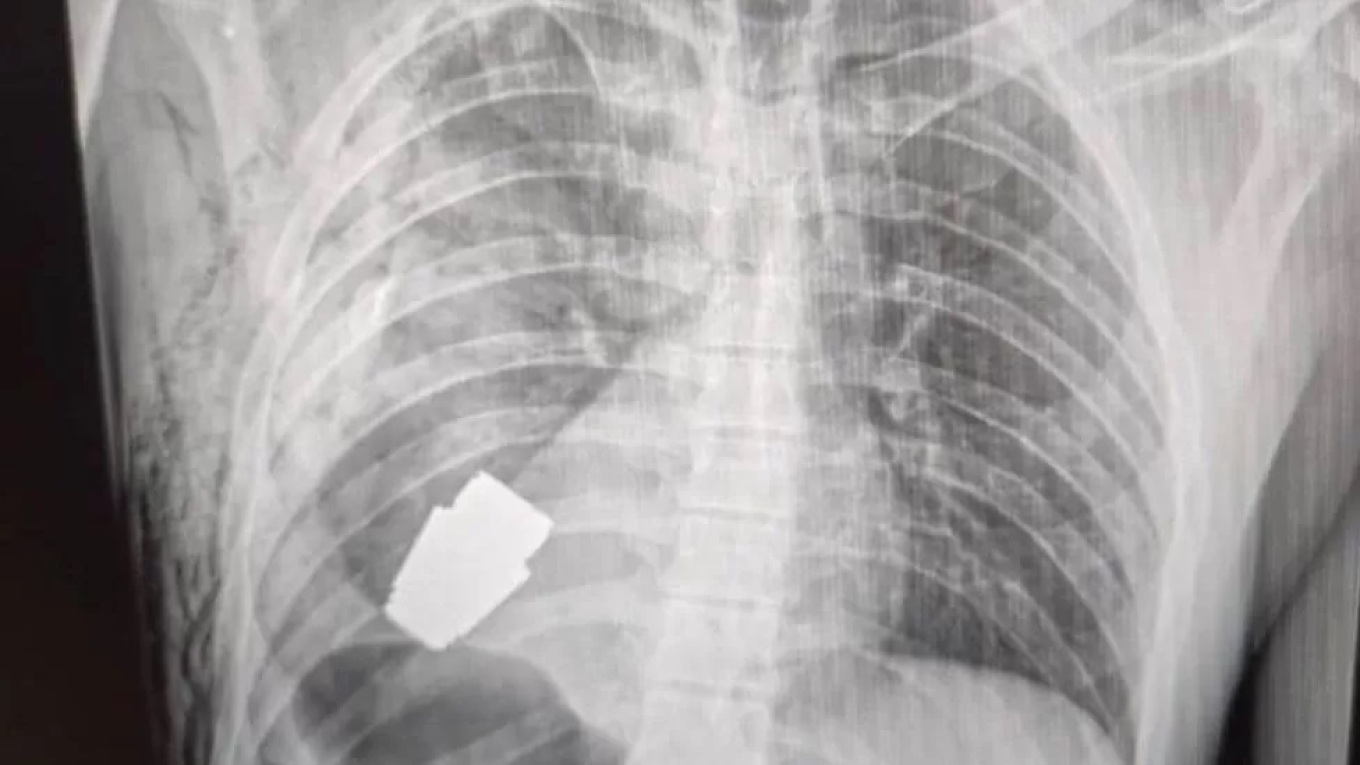

Στην ακτινογραφία φαίνεται η χειροβομβίδα στο στήθος του στρατιώτη πολύ κοντά στην καρδιά του.

Άγνωστο είναι, όπως αναφέρει το BBC, πώς βρέθηκε η βομβίδα, τύπου VOG με μέγεθος τέσσερα εκατοστά, στο στήθος του άνδρα.